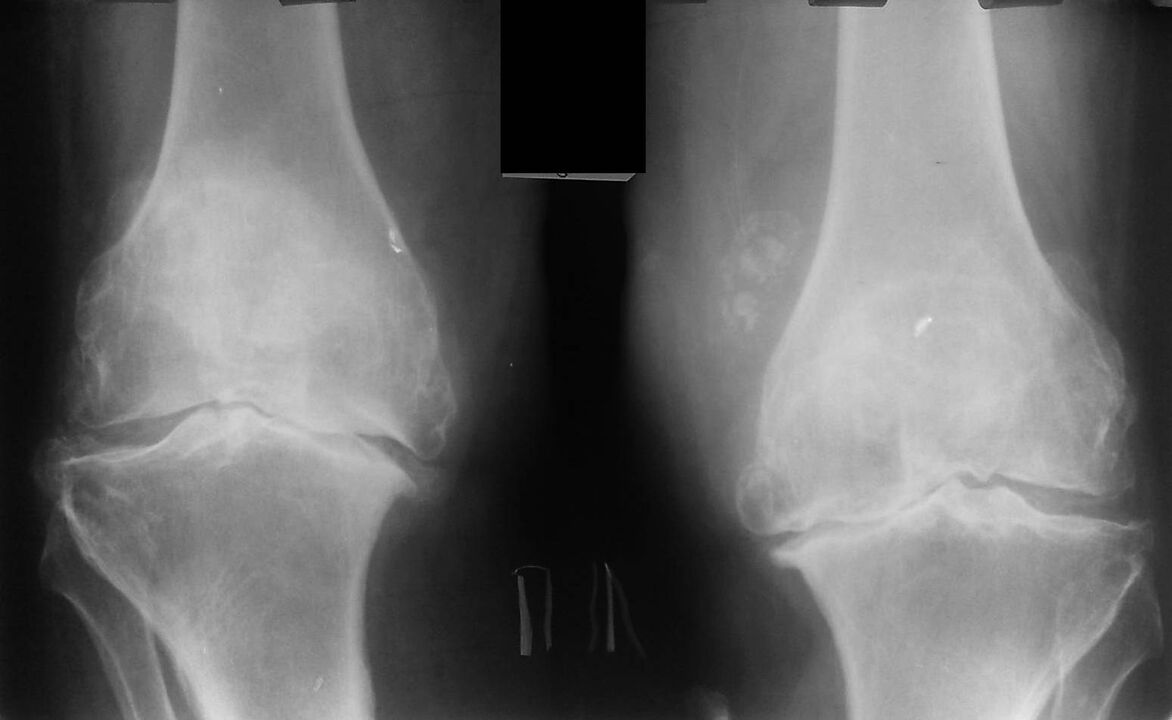

Тази диагноза се поставя въз основа на оплаквания на пациента, данни от прегледа, палпация на болната става и рентгеново изследване.

Рентгеновата снимка е стандартен изследователски метод, който ви позволява да потвърдите диагнозата, да установите степента на патологични промени, да наблюдавате динамиката на процеса, а също така ви позволява да изключите други патологични процеси (например тумори) в тибията и бедрената кост .

Трябва да се отбележи, че първичните промени в структурите на колянната става на рентгенови снимки може да липсват. Впоследствие се определя стесняване на ставното пространство и уплътняване на субхондралната зона. Ставните краища на бедрената кост и особено на пищяла се разширяват, ръбовете на кондилите стават заострени.

Допълнителни диагностични методи са CT (компютърна томография) и MRI (магнитен резонанс), които позволяват по-подробно изследване на патологичните промени в костните структури и идентифициране на промени в меките тъкани.